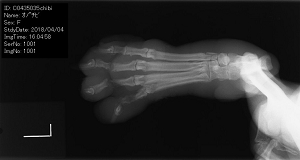

みやこ町犀川で、後足にケガを負っているビーグル犬を、近所の人が保護しました。保護した人は、その犬を動物病院に連れて行きました。

ケガはワナによるもので、

レントゲン検査の結果、左後足4本の指の内、3本が関節で完全に断裂していました。甲の皮膚は失われて、足首にはワイヤーで絞められた跡がくっきりと残っていました。幸いなことに、足先までの機能には支障が及んでいませんでした。

皮膚の移植など、治療のために、2週間の入院を要しましたが治療はとても上手くいきました。手当が遅れていたら、足の切断も免れませんでした。